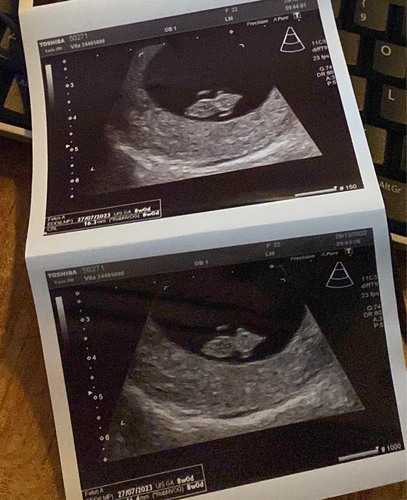

Ik was al verder dan gedacht en met 9+4 te laat voor de theorie, maar je ziet hier wel 2 lichte plekken en in het echt is het nog een stuk duidelijker verschil. Die langrekte witte streep links/onder bij de baby is waar je dan op hoort te letten. (Dit was bij mij uitwendig. En als het dus optijd zou zijn was het een jongen volgens de theorie.)

Ah zo ik heb de vorige echo’s van de jongens opgezocht en doe lagen op de echo helemaal rechts dus dat klopt het bij ons 2 keer niet 😅 of de computer draait het automatisch weer goed ipv spiegelbeeld